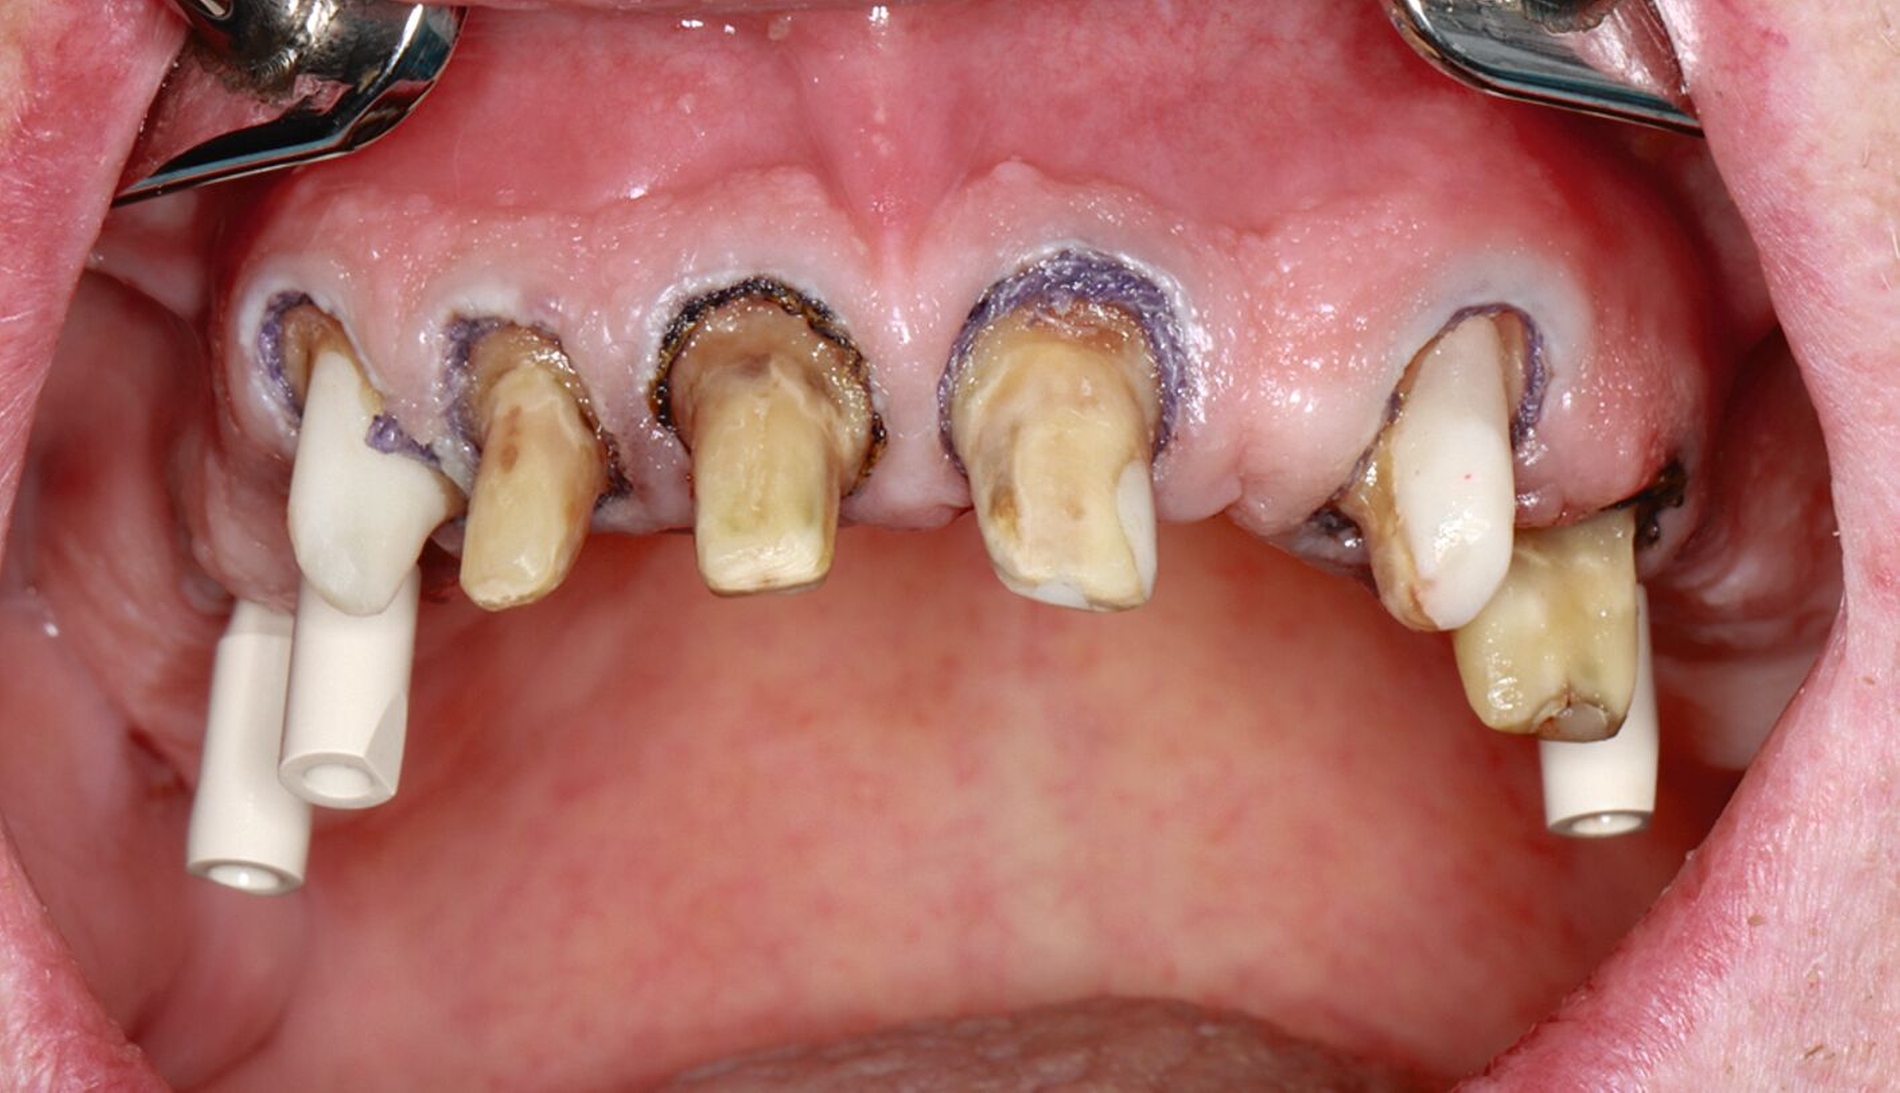

Die Stümpfe wurden folglich zur Aufnahme von Teleskopkronen präpariert und mittels Doppel-Fadentechnik für die konventionelle Abformung mit dem Polyether vorbereitet. Nachdem das zahntechnische Labor die NEM-Primärteleskope hergestellt hatte, wurden sie am Patienten anprobiert und mit einem Tropfen provisorischen Zements auf den Stümpfen fixiert (Abbildung 5a), um sie anschließend in der Fixationsabformung mit abzuformen (Abbildung 5b).

Nach Durchführung einer dentalen Volumentomografie (DVT) wurden daher zahnärztliche Implantate in Regio 14, 15 und 25 im Sinne einer verkürzten Zahnreihe geplant und inseriert (Abbildung 7). Nach dreimonatiger subgingivaler, konventioneller Einheilzeit wurden die Implantate freigelegt. Zwei Wochen später begann man die vorhandenen Primärkronen zu entfernen. Die Stümpfe wurden nachpräpariert und es wurden erneut Fäden gelegt (Abbildung 8a und 8b).